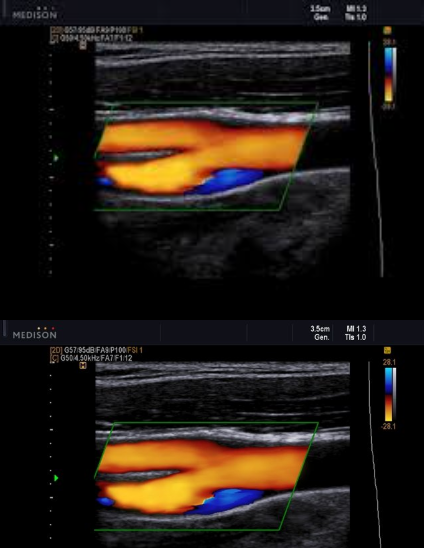

Patient presents with recent history of syncope. New onset of HTN and HX of smoking 1 pack per day (ppd) x 25 years.

Carotid ultrasound exam ordered. Considering following questions and please answer.

1. In patient presentation, which item is the symptom for carotid ultrasound exam?

2. In patient presentation, identify the risk factors for atherosclerosis and carotid artery disease.

3. Consider image, which vessel contain some blue colors?

4. Is the 'blue' pathological?

5. What is the color blue representing?

Syncope

HTN and smoking

Prox ICA (bulb)

no

eddie currents from flow reversal in bulb